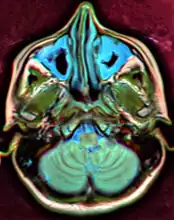

A CT scan showing sinusitis of the ethmoid sinus